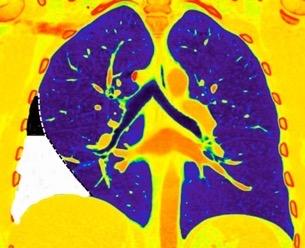

Signos radiológicos TC

Hallifax RJ et al. State-of-the-art: Radiological investigation of pleural disease Respiratory Medicine 2017

Nivel hidroaéreo o burbujas

Forma lenticular o elíptica Ángulos obtusos

> Grasa Extrapleural (60-80%)

Situación no gravitacional (no siempre)

Compresión de estructuras pulmonares

Límite muy bien definido Tabicación

Patrón ecográfico de empiema

Empiema

El derrame paraneumónico se convierte en complicado en 5-10% de los casos

Engrosamiento de la pleura parietal 36/ 59 exudados (61%) 56% de D. paraneumónicos 100% de empiemas Especificidad.. 96%.

Exudado versus trasudado.

Aquino SL, et al. Pleural exudates and transudates: diagnosis with contrast-enhanced CT. Radiology 1994

Signo de la Pleura separada “Split pleural sign”

Capas pleurales de grosor uniforme realzadas por el contraste

Dr. César Pedrosa

No específico de empiema. Indica “exudado”. 68% de pacientes con empiema pleural.

Capas pleurales de grosor uniforme

Realce grasa extrapleural (30%)

> Grasa Extrapleural. (60-80%)

Kraus GJ. Split pleural sign. Radiology 2007